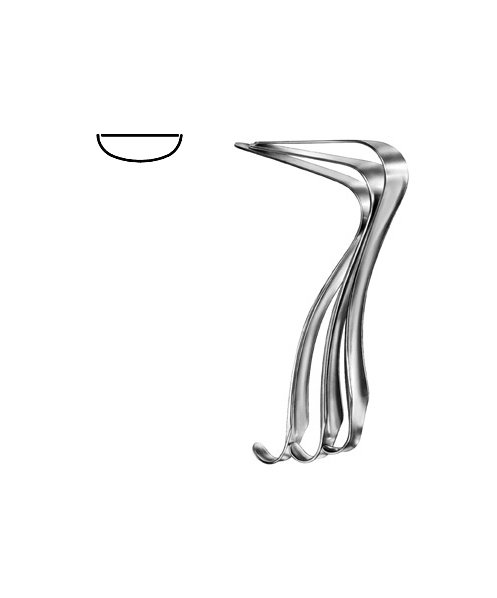

- Gynecology, Surgical Instruments

Endocervical Speculum

- Size : 25 CM - 9 3/4"

- Read more